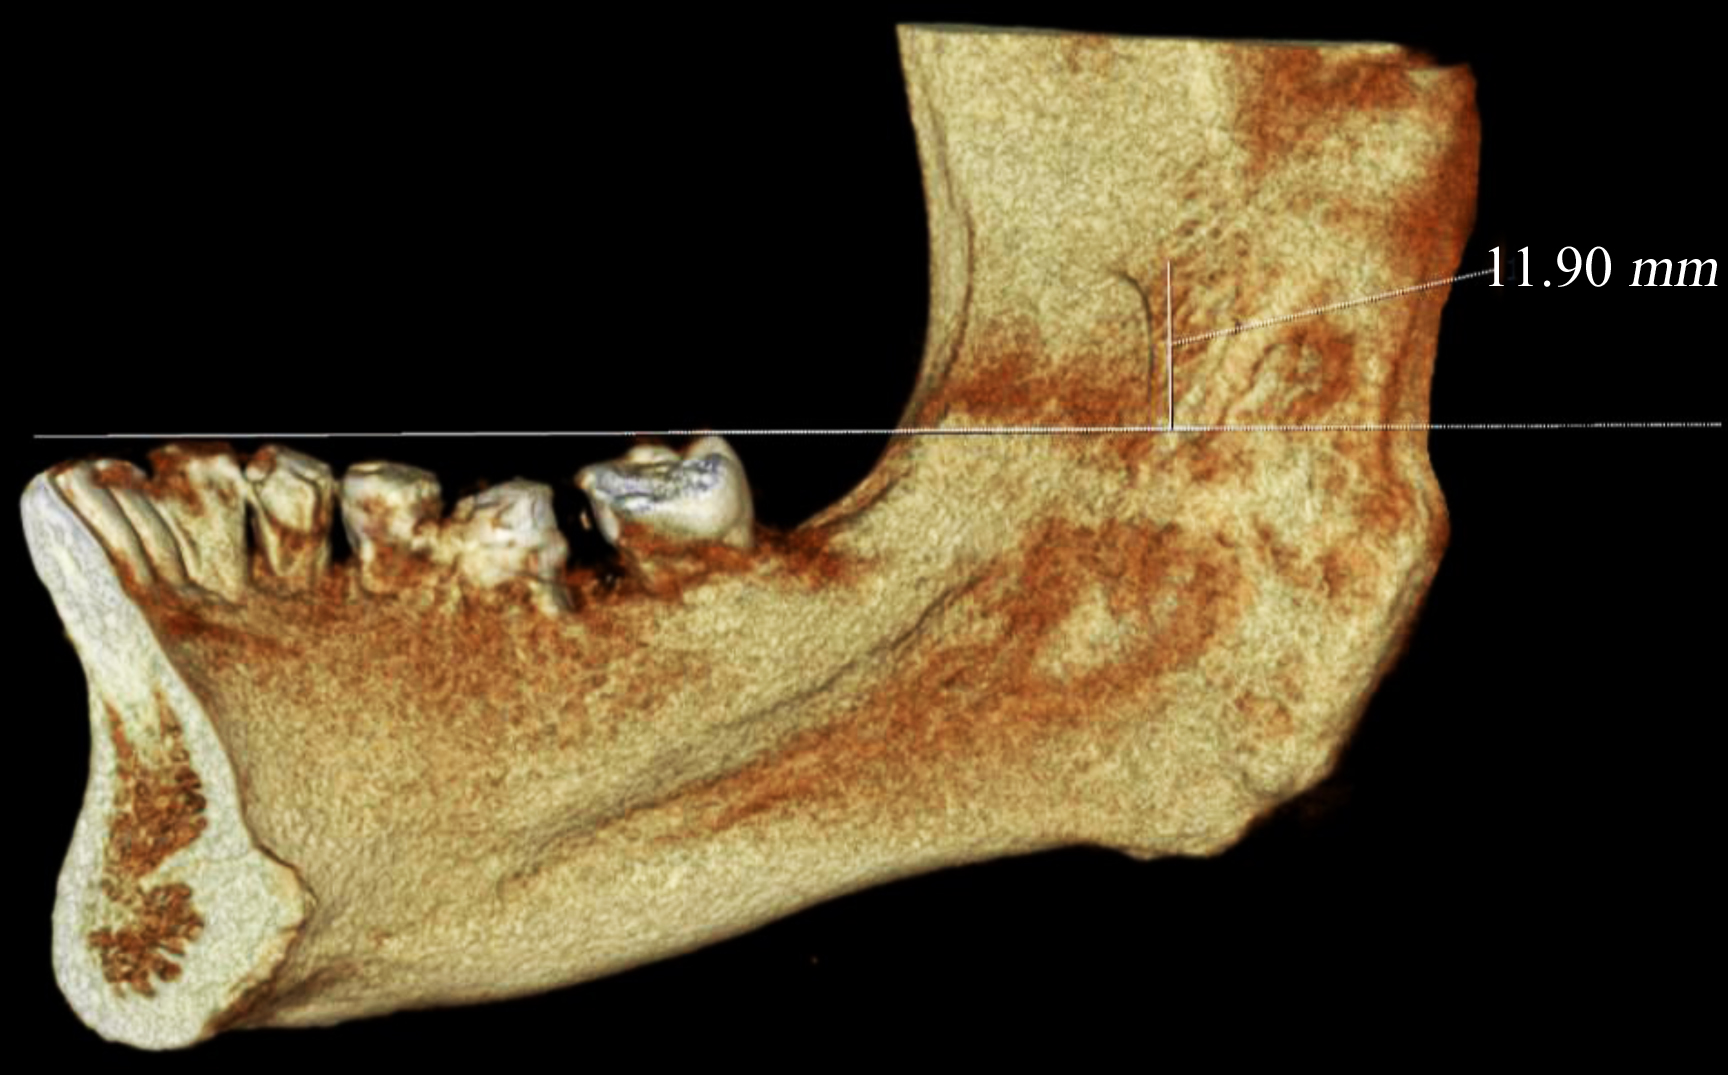

The distance between the occlusal plane and the center of MF was also measured on CBCT scans. Prior to the measurements, the 3D position of the mandible was standardized. For this purpose, the occlusal reference plane was drawn from the tip of canine and mesiobuccal cusps of mandibular first and second molars parallel to the horizon. The distance between the midpoint of the MF and the occlusal plane was then measured (6) (Figure 2).

Figure 2. Distance between the occlusal plane and mandibular foramen measured on CBCT scans in NNT Viewer software.